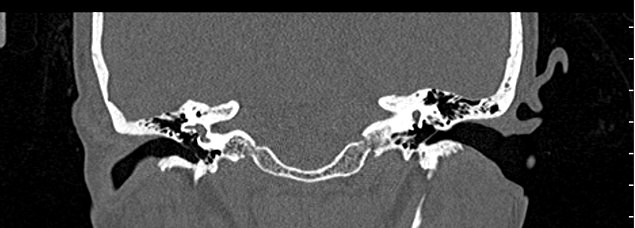

Мультиспиральная КТ позволяет детально визуализировать все вышеперечисленные анатомические структуры височных костей, диагностировать заболевания среднего и внутреннего уха.

КТ наиболее информативна при черепно-мозговых травмах, воспалительных заболеваниях уха, опухолевых процессах этой области. При компьютерной томографии возможно проследить ход барабанной перепонки, оценить структурность и положение слуховых косточек (молоточка, стремечка и наковальни), оценить объем и расположение содержимого в антральной клетке или ячейках сосцевидного отростка височной кости.

- показать четкую картину строения среднего уха.